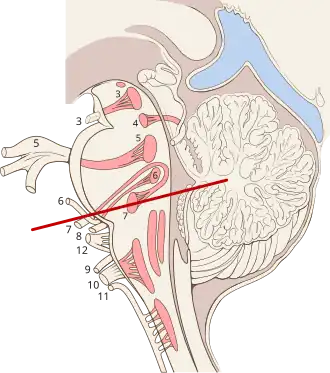

Brain stem sagittal section (11 visible near bottom center) | |